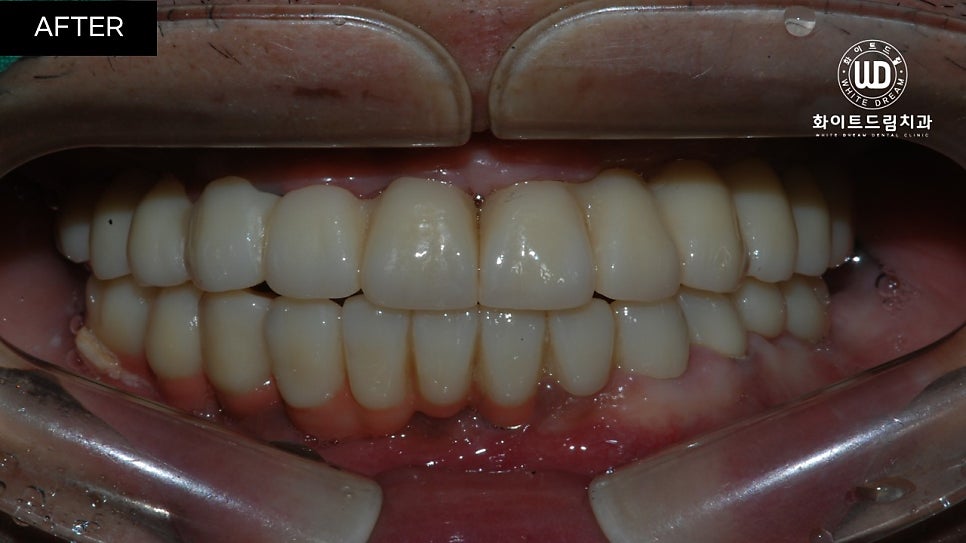

중간 지주대를 픽스처에 연결해주고 2주뒤 최종 보철물까지 올려주니 실제 치아와 비슷하게 기능적, 심미적으로 회복되었습니다.

치아 정면 전/후 사진을 함께 살펴보면, 임플란트 식립 모양이 돔 형태로 예쁘게 이식된 것을 확인할 수 있습니다. 전체 임플란트는 교합면을 잘 선정하는 것이 중요합니다. 교합면은 자연치가 맞물리는 면으로, 너무 높으면 턱관절에 무리가 갈 수 있고 저작할 때 고르게 분산되지 않습니다.

반대로 너무 낮으면 구강 내부 혀나 볼을 씹어 상처가 나고, 턱 모양에도 영향을 끼칠 수 있기 때문에 정밀 검사 후 적절하게 식립하는 것이 좋습니다.

환자분께서 아직 젊은 나이임에도 불구하고 좋지 않은 치아상태로 인하여 자신감이 많이 하락하신 상태였는데, 씹는 힘은 물론 외적인 모습까지 복구가 되어 만족스러운 결과를 얻으셨습니다.